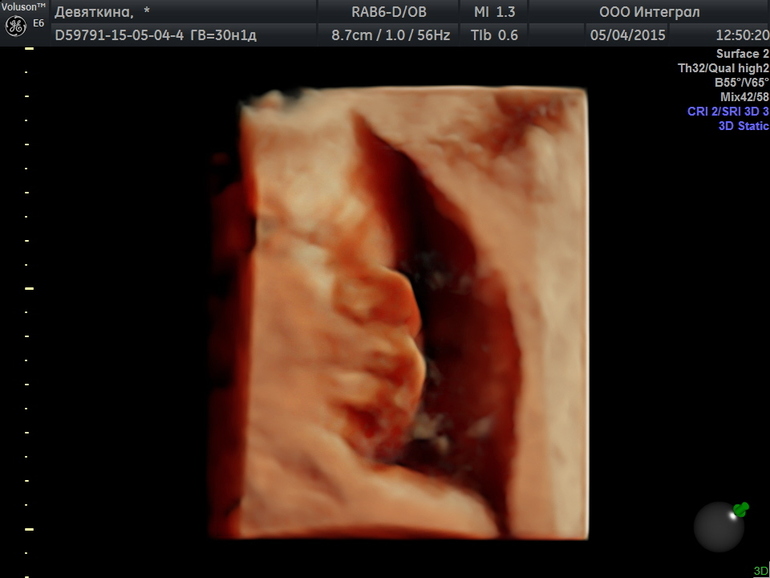

А на последней на оранжевой пальчики на ножке) Кстати ножка 5см.